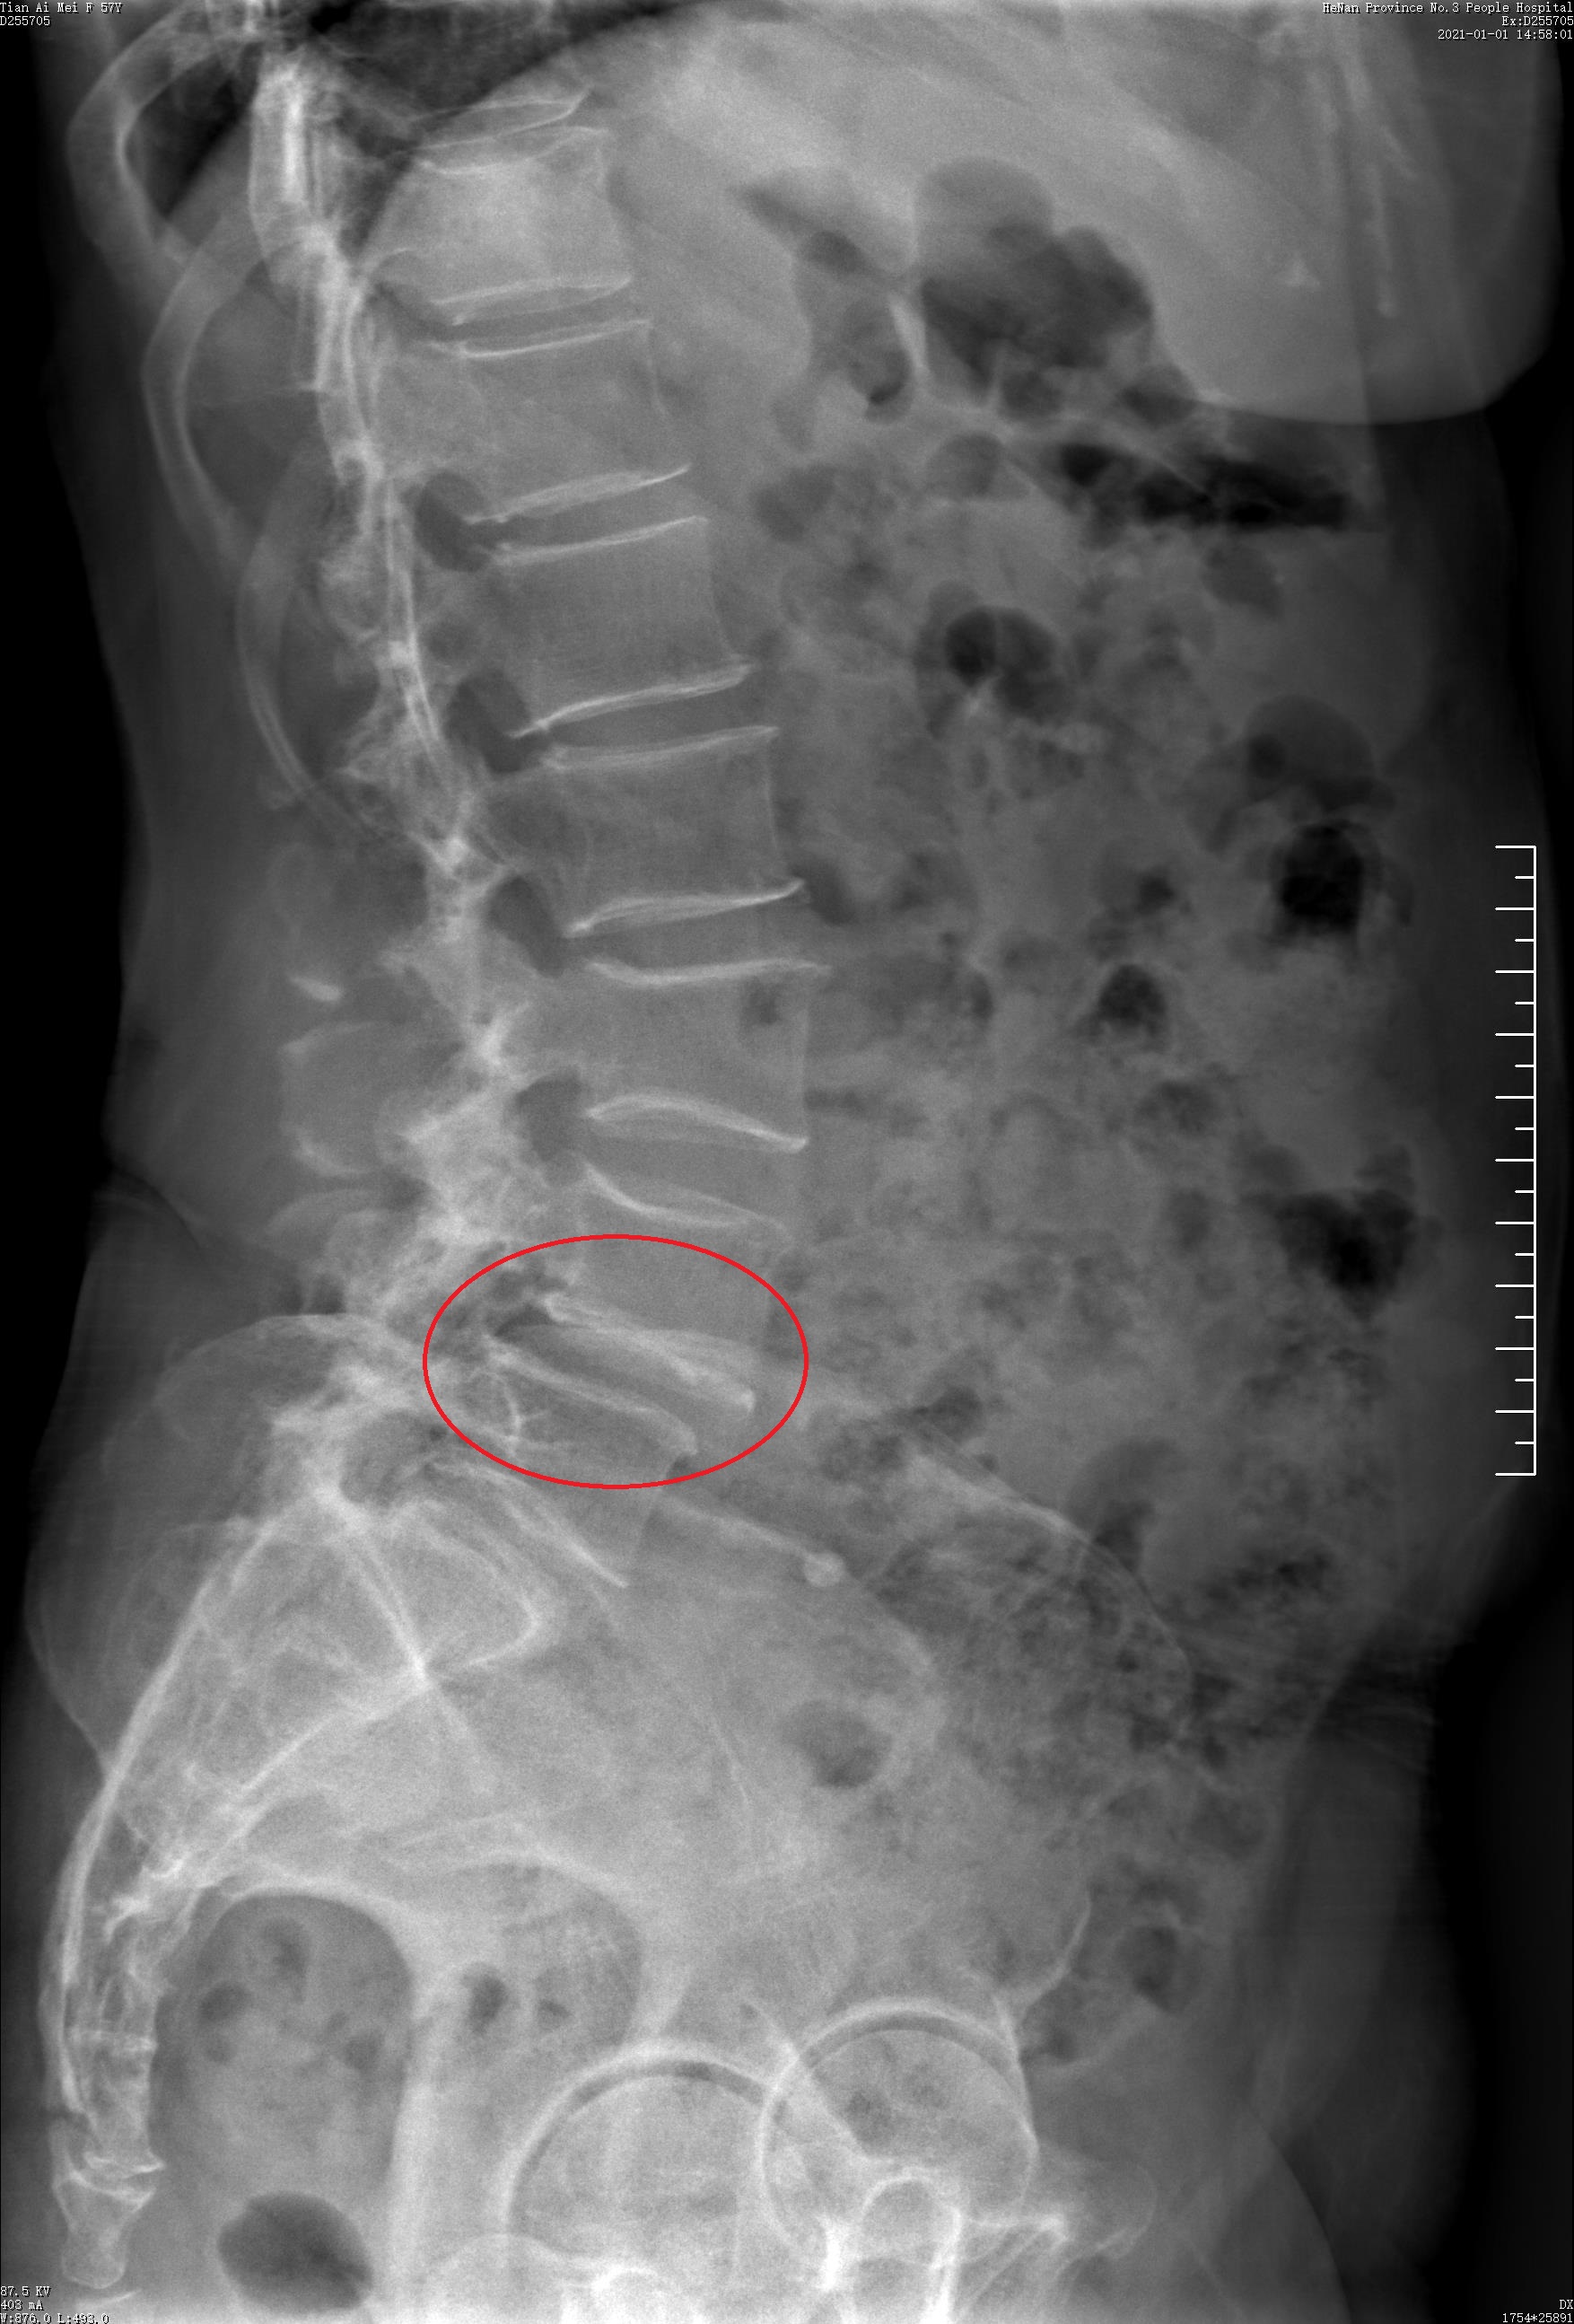

腰椎滑脱症

患者,女,57岁,2年前出现活动后腰部疼痛,保守治疗后稍缓解,1年前开始出现左臀部酸困不适,半个月前出现腰部及左髋部疼痛明显加重,伴左下肢麻木不适,为求进一步治疗来到我院椎间盘中心。

入院后,完善相关检查,诊断为腰椎滑脱症(L4/5),予以实施了全麻下UBE技术L4/5镜下融合滑脱复位内固定术。

术前侧位片

术后侧位片